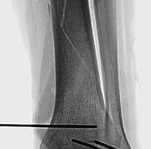

When a diaphyseal fracture propagates into the distal articular block, the injury transcends the typical treatment algorithms reserved for isolated tibial shaft fractures. Intramedullary nailing, the gold standard for diaphyseal fractures, becomes fraught with complications such as articular malreduction, propagation of intra-articular fracture lines, and inadequate distal fixation. Therefore, plate fixation—often utilizing minimally invasive percutaneous plate osteosynthesis (MIPPO) techniques—emerges as the primary definitive treatment modality. In the setting of an AO/OTA 43C3.3 fracture, where the articular surface is multifragmentary and completely dissociated from the diaphysis, the surgeon must meticulously reconstruct the joint surface before bridging the diaphyseal segment.

Biomechanically, the transition from the rigid diaphysis to the cancellous metaphysis creates a stress riser. When utilizing plate osteosynthesis for a fracture extending from the shaft into the plafond, the construct must fulfill two distinct biomechanical roles: absolute stability at the articular surface and relative stability along the multifragmentary diaphysis. Absolute stability of the articular block is achieved through anatomic reduction and interfragmentary compression using lag screws. This reconstructs the joint and provides a solid foundation.